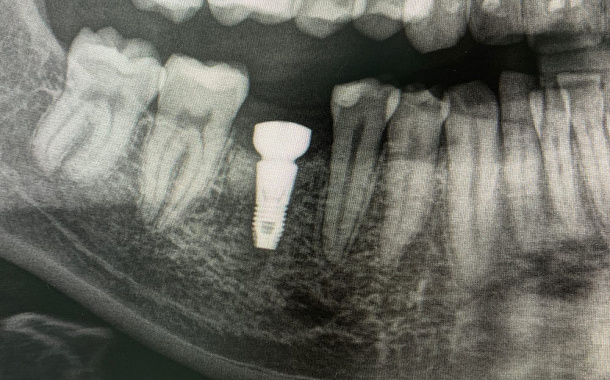

По 3D компьютерной томографии определяет возможность установки имплантата, немедленной фиксации временной коронки в день операции и объем пластических манипуляций. Совместно с врачом-стоматологом ортопедом планирует вид ортопедической конструкции и положение имплантата.

Компьютерная томография в формате 3D - важный диагностический инструмент стоматолога. На полученном объемном снимке стоматолог видит все нюансы вашей зубочелюстной системы: состояние костной ткани челюстей, зубов и височно-нижнечелюстного сустава. Именно томография позволяет доктору составить план и объем предстоящего оперативного вмешательства.

- Установка имплантата в запланированном положении, заполнение пространства лунки костно-пластическим материалом, наложение швов.

Врач решает это в ходе обследования, а в некоторых случаях и в ходе операции. В случае получения необходимой первичной стабильности зубного импланта (т.е. усилие с которым была проведена установка имплантата в кость), в день операции фиксируется временная ортопедическая конструкция.